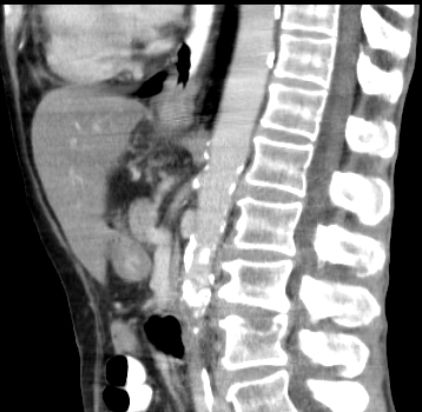

LK-Metastasen im aorto-pulmonalen Fenster ![]() | ||